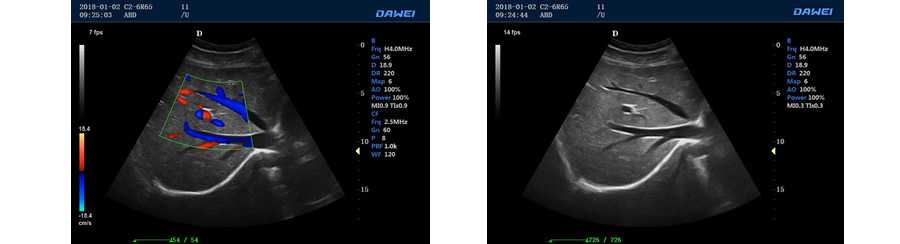

●彩色多普勒血流成像單元

多普勒模式

具有PW脈沖波多普勒和CW連續波多普勒